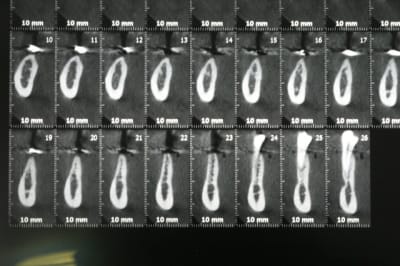

dans le même sujet, j'aurais aimé avoir votre avis sur ce cas. J'hésite entre une ROG avec membrane titane ou une greffe d'apposition.

04/11/2011 à 13h58

j'ai 16mm entre les dents, mais 9mm de hauteur de crête pour la 47.

pour ce qui est de l'expansion, je n'ai jamais tenté l'exercice, et les corticales me paraissent bien épaisses.

Dans ce cas de figure, sans aucun doute, Régénération avec vis d'otéosynthèses ( en toile de tente) + membrane osseoguard résorbable.